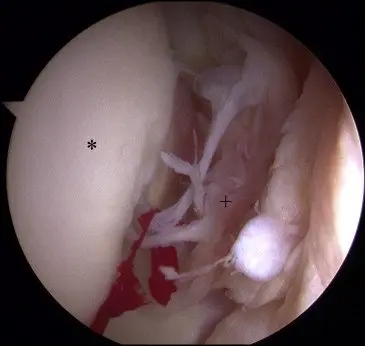

A diagnostic arthroscopy is performed, switching portals frequently to access all parts of the joint. Any additional pathology in the joint is addressed before LT reconstruction. The LT is examined and probed upon identification of a complete tear (Fig 1 and Video 1); the stump in the acetabular fossa is cleared with the Nav X ablation device (Arthrex, Naples, FL) and a shaver (Fig 2).

Fig 1. Arthroscopic view of left hip showing complete tear of LT. The patient is in the supine position, with visualization of the central compartment of the hip through the anterolateral portal. (Asterisk, femoral head; plus sign, LT stump.)